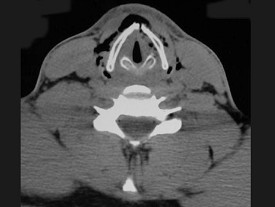

11.27歲男性,開車外出在高速行駛時翻車,呼吸困難,喉部腫脹,CT檢查如圖所示,請選擇正確的描述或診斷  (    )

正確答案:ABCE